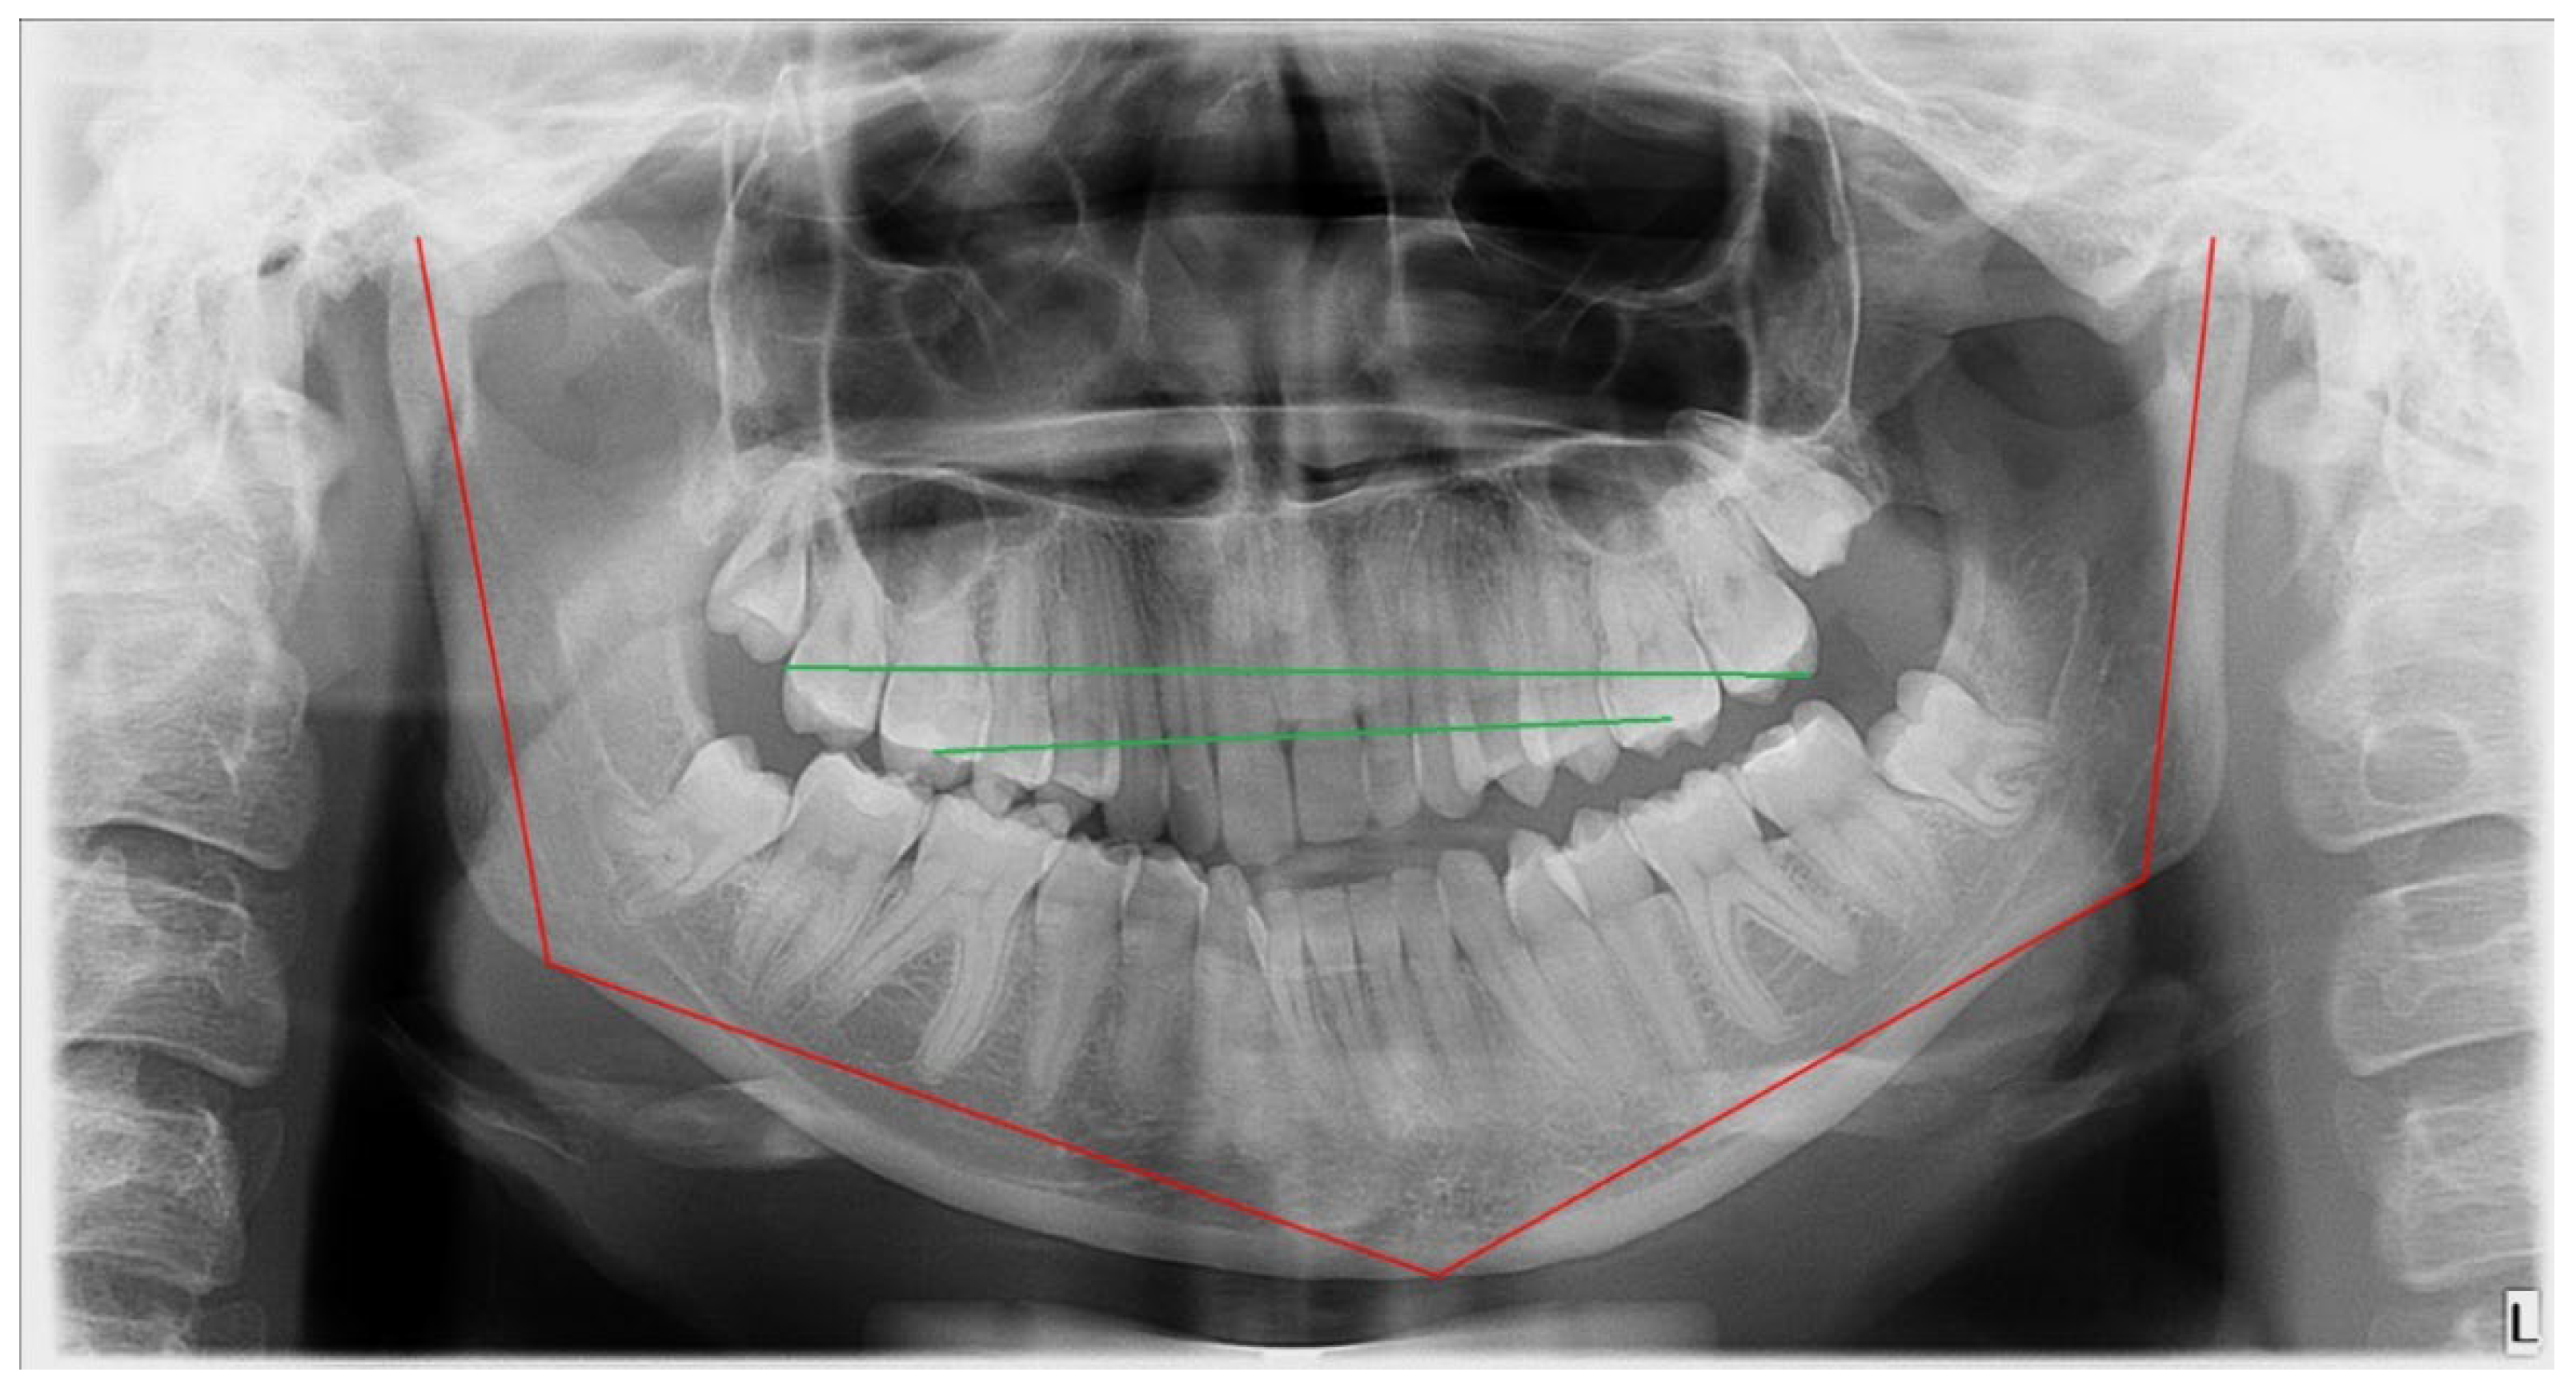

G—gonial angle, presence of antegonial notch (Figure 1)—present on the contralateral side from the bone overgrowth in the mandible angle, manifested as angle curvature, rather than a smooth oval angle in the affected overgrowth side;

Figure 1. Presence of an antegonial notch on the healthy side (pointed with red arrow).